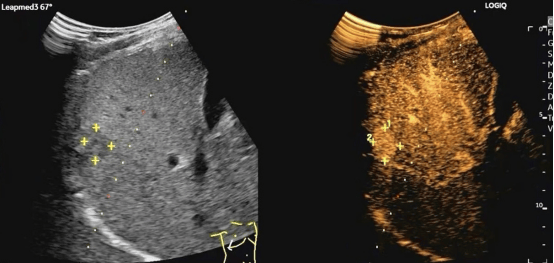

2.超声定位:术者将在超声下为患者精准确定穿刺点和穿刺路径,标记肿瘤位置;

图为我院肿瘤内科开展消融手术现场

术前

术后